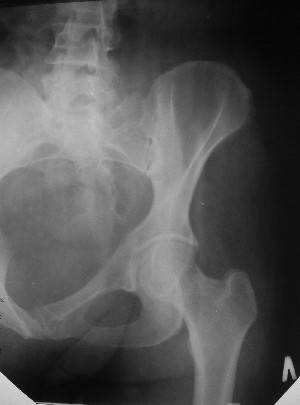

Из анамнеза: в ноябре 2002г. оступилась,упалана трап самолета (на верхней площадке, сразу при выходе из салона) на правый тазобедренный сустав, а затем - вниз на землю на ноги и ягодицы. Потеряла сознание от боли. Доставлена в больницу по месту жительства, лечилась консервативно с диагнозом кокцигодиния.На рентгенограмме от 27.11.02г. вывиха копчика не определяется (снимок идентичен представленной R-грамме от28.11.03г., кроме этого есть нормальная R-грамма копчика в боковой проекции).Через три недели стала ходить, но привести правую ногу в тазобедренном суставе не могла. Сейчас ходит отведя кнаружи правое бедро и голень, как ножку циркуля (фото 1). Неврологических нарушений нет. По просьбе врачаможет на 30-40 секунд поставить ноги вместе (фото 2). При этом испытывает сильную тянущую боль и ощущение "вывернутости" в правом тазобедренном суставе. Эти ощущения заставляют вновь отвести бедро. В положении лежа разогнуть бедро полностью не может из-за болей в ягодичной мышце (фото 3). Сгибание также ограничено из-за болей (фото 4). Отведение в положении лежа возможно в том же объеме, что и стоя (фото 5). Заподозрен старый разрыв правого крестцово-подвздошного сочленения.Выполнено R-исследование и КТ(в приложении). По-поводу деформации лонного сочленения выяснен гинекологический анамнез. Роды одни, нормальные в 22 года. Из роддома выписана на 8 сутки, нарушения походки не было, R-графия таза не проводилась. Вопросы на обсуждение: 1. Диагноз либо алгоритм дальнейшего обследования. 2. Лечебная тактика (в первую очередь возможность и целесообразность оперативного лечения).

Отсутствие изменений сустава на КТ и обычных рентгенограммах, стойкие боли и ограничение подвижности в суставе - симптомы, характерные для повреждения ацетабулярной губы. ЯМР с контрастом или без должны прояснить картину.

Уважаемый Юрий Алексеевич, сделаны ли пациентке более дистальные срезы КТ с захватом области тазобедренного сустава? Учитывая давность травмы, могли присоединиться и дистрофические процессы в субхондральной кости головки и впадины. Изменения в капсуле будут хорошо видны на УЗИ, особенно в сравнении со здоровой стороной. Эффективность лечебно-диагностического введения гормональных препаратов, на мой взгляд, сомнительна ввиду давности патологического состояния. При такой стойкой и давней контрактуре без операции вряд ли можно обойтись. Под наркозом амплитуда на разгибание должна увеличиться, усилить эффект можно тено-миотомиями заинтересованных групп мышц, капсулотомией + в послеоперационном периоде хорошее консервативное противовоспатлительное лечение с укладками на разгибание.Что мешает приведению пока не ясно, во встретившихся в нашей работе аналогичных ситуациях причиной был формирующийся медиальный остеофит головки, выталкивающий её из впадины.